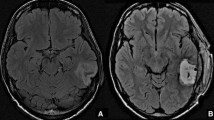

Disease progression at the site of the original tumor was identified in only 4 (33%) patients (median 23 months, range 8–25 months). At the time of this manuscript preparation, only 4/12 (33%) of patients have died. Based on the statistical considerations above 9/10 (90%) of our first 10 patients and 10/12 (83.3%) had 6-month PFS. For all 12 subjects, the median PFS was 9.10 months, and the OS was 17.6 months. 4/12 (33%) of patients are still alive for more than two years and our longest surviving patient currently is alive at 60 months. Importantly, in no case was there worsening MRI enhancement within the flap suggestive of tumor infiltration for the duration of the study (see Fig. 2).

(Upper row) T1 post-contrast MRI of one of the study patients: Pre-operative scan showing an enhancing lesion at the left temporo-occipital region; Post-operative scans at 1, 30, 90, and 180 days after surgery, showing no recurrence or enhancement at the resection site cavity lined by the flap. (Lower Row) T1 post-contrast MRI of one of the study patients with recurrence in the surgical cavity: Preoperative scan showing a right parietal lesion; Post-operative scan showing the flap lining the resection cavity. Pre-Flap Removal scan showing flap enhancement as seen in a follow-up scan done at 25 months. Post-operative scan done on POD 1 after removal of the flap. (MRI: Magnetic Resonance Imaging; POD: Post-operative Day)

In 4/12 cases, the tumor recurred near the initial tumor bed (Fig. 2), with a median time to recurrence of 23 months (range 8–25 months), well beyond the 6 months defined as one of the primary safety points (Supplementary Table 4). In 3/4 of those cases, patients underwent reoperation (biopsy was done in the 1 case). The tumor was re-resected and the flap was removed and sent for histopathological analyses.